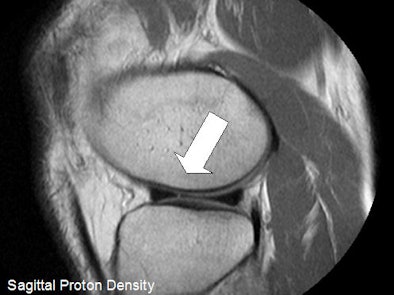

| Above, sagittal proton density-weighted image through the lateral meniscus from a 52-year-old male with interior knee pain. There is a short radial tear, which was seen only on the sagittal MR image and was present on the arthroscopy, making the image a true positive. Below, midsagittal proton density-weighted image is of the ACL of a 49-year-old male. The ACL appeared morphologically normal on MRI, but demonstrated laxity in arthroscopy. An orthopedic surgeon ruled a partial tear, making the image a false negative. Images courtesy of Asheesh Harsha and New York University. |